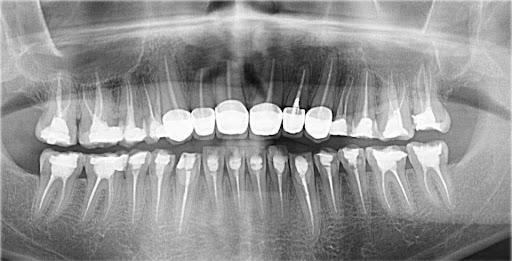

Trước khi bước vào thực hiện làm răng sứ, các bác sĩ tại Nha khoa HanSeoul sẽ tiến hành thăm khám tổng quát để xác định được tình trạng răng miệng của khách hàng. Sau đó tiến hành chụp hình cận răng và hướng dẫn khách hàng chụp phim X-quang CT để có hình ảnh trực quan nhất về cấu trúc răng – hàm. Từ đó xác định chính xác được mức độ tình trạng của răng cần khắc phục.